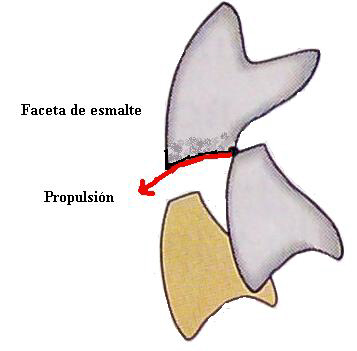

Signos: Facetas parafuncionales y ausencia de

guía anterior

Cuando los cambios producidos en la estructura del esmalte alteran la

función (Guía anterior) ó facilitan la acción de otros mecanismos

destructivos, estamos en presencia de una faceta patológica.

Así como la "mancha blanca" lo es en el

proceso de caries dental, la faceta parafuncional debe ser diagnosticada

en forma precoz

para

prevenir alteraciones posteriores de complicada solución.

Tipo

I

(de esmalte):

Son las más difíciles de diagnosticar, por su forma sutil de

presentarse.